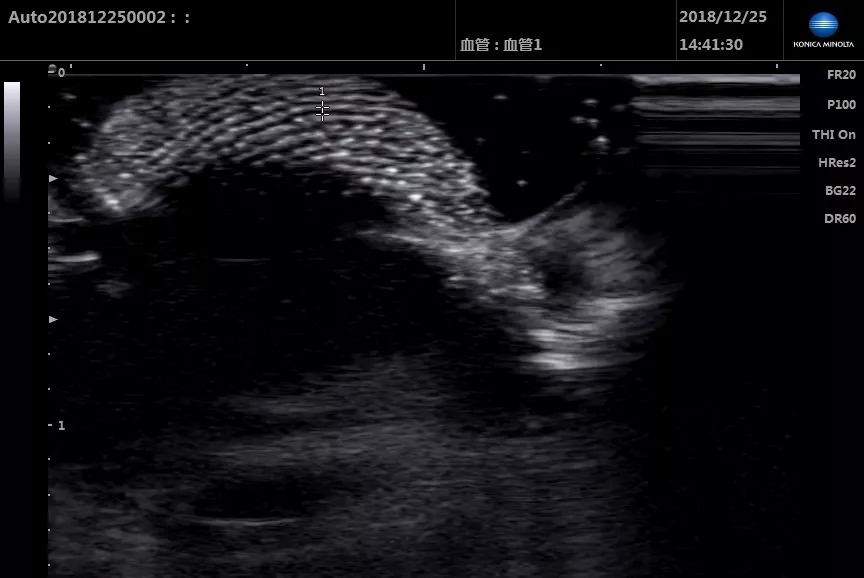

柯尼卡美能達攜明星產品SONIMAGE HS1助力Workshop環節,對肩、肘、腕、髖、膝、踝關節實際操作超聲檢查。

參會醫生學習熱情高漲,圍在帶教專家周圍,根據超聲屏幕上顯示的圖像,不斷發出提問,專家一一耐心講解。